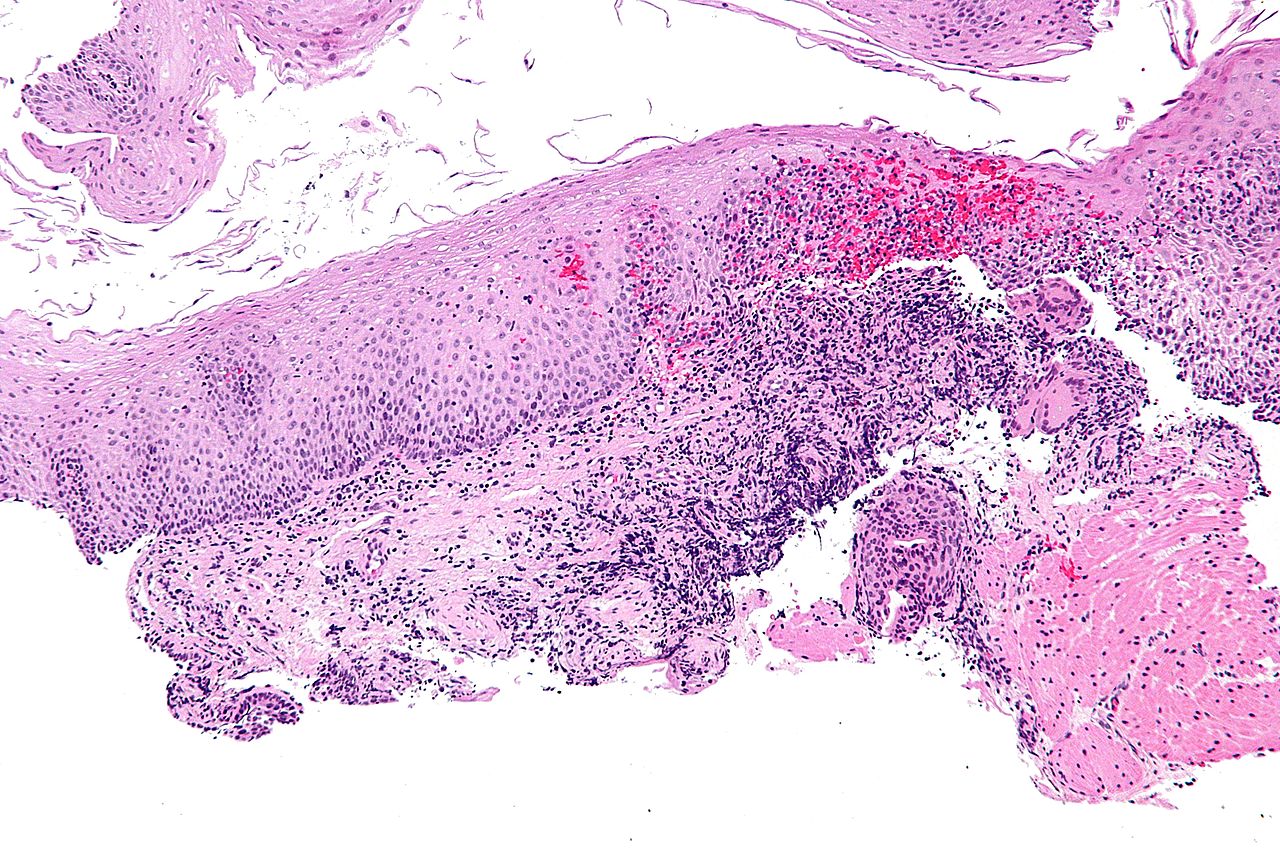

Boala Crohn consta in inflamatia intestinului, ea poate afecta orice segment, insa cel mai adesea se observa la nivelul terminal al intestinului subtire (ileon) sau la nivelul terminal al intestinului gros (colon).

Simptomele bolii Crohn sunt adesea inselatoare, iar diagnosticul este pus destul de greu, pentru ca semnele de boala apar treptat. Boala Crohn este de patru tipuri: usoara, moderat – severa, severa sau inactiva. Printre simptomele bolii mentionam:

- colonoscopie sau sigmoidoscopie. Ambele analize constau in introducerea prin intermediul sfincterului anal a unui tub lung flexibil dotat cu o camera video conectata la un monitor ce reda imagini ale intestinului in timp real. Cea mai indicata in cazul suspectarii de boala Crohn este colonoscopia, deoarece ea spre deosebire de sigmoidoscopia ce investigheaza ultimii 60 de centimetri ai intestinului gros, analizeaza intregul colon;

Boala Crohn se poate agrava de-a lungul timpului, putand duce si la deces in cazul in care ea a dezvoltat complicatii. Persoanele suspecte de boala Crohn sau care au fost diagnosticate cu boala Crohn trebuie sa urmeze in mod frecvent analize pentru determinarea prezentei sau absentei cancerului de colon.